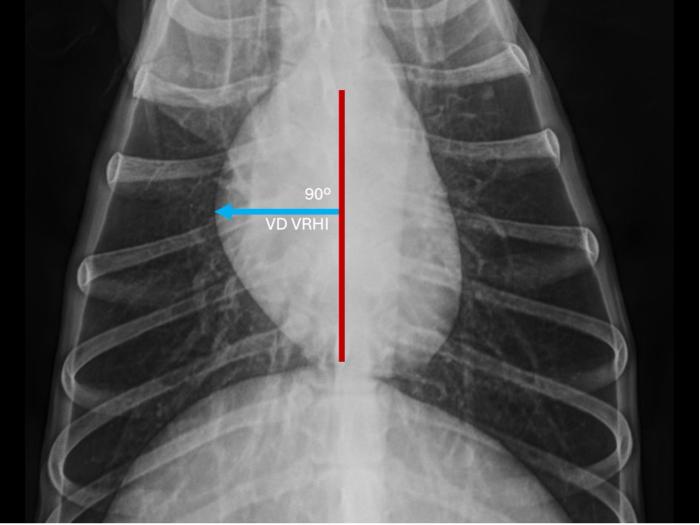

La determinación del VRHi se basó en el protocolo descrito por Puccinelli y colaboradores(2024). En la proyección LLD, el eje largo y el eje corto máximo de la silueta cardíaca se identificaron como se describió previamente para la escala cardíaco vertebral o índice de Buchanan (Buchanan & Bücheler, 1995). En el eje corto, se midió la distancia desde el margen craneal de la silueta cardíaca hasta la línea de intercepción del eje largo. Posteriormente, la misma línea se colocó sobre las vértebras torácicas comenzando en el borde craneal de la cuarta vértebra torácica, y se estimó el número de cuerpos vertebrales (CV). En la vista VD, el eje longitudinal torácico se trazó como una línea superpuesta a la columna vertebral. En el eje transversal, se calculó la distancia desde el margen derecho de la silueta cardíaca hasta el eje longitudinal torácico y se midió contra las vértebras torácicas en las vistas laterales, como se describió anteriormente (Figura 1 y 2).

Representación de la determinación del índice cardíaco vertebral derecho (VRHi) en proyección ventro-dorsal (VD) en un perro parasitado por Dirofilaria immitis y que sufría de hipertensión pulmonar. Valor de 2,5 cuerpos vertebrales al trasladar la determinación sobre las vértebras torácicas comenzando en el borde craneal de la cuarta vértebra torácica en proyección latero-lateral derecha (línea de color azul).